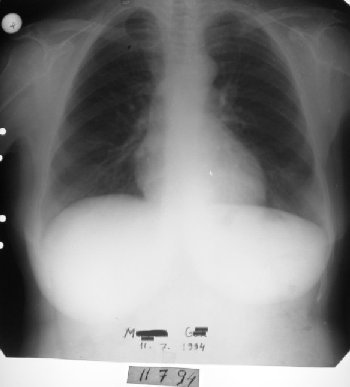

53 yaşında kadın hasta • 9 ayda tam iyileşme

1991 yılında az diferansiye fibröz malign mezotelioma teşhisi konulan 53 yaşındaki kadın hasta, çok düşkün haldeyken immünomodülatör tedavi ile 9 ayda tam iyileşme sağladı. 2000 yılında hasta remisyondaydı ve 9 yıl boyunca hastalık belirtisi göstermedi.

1994-2000 - Uzun Dönem

Remisyon devam ediyor (9 yıl)

Radyolojik bulgular normale yakın hale gelmişti ve immünomodülatör tedaviyi kesmesi önerildi.

1994 (3 yıl sonra): Takipte yalnızca küçük bir blokaj dışında bulgu yoktu

2000 (9 yıl sonra): Hasta remisyondaydı

Malign mezotelioma tamamen kontrol altına alındı ve uzun dönem remisyon sağlandı.

• Radyolojik normalleşme (9 ay)

• 9 yıllık uzun dönem remisyon